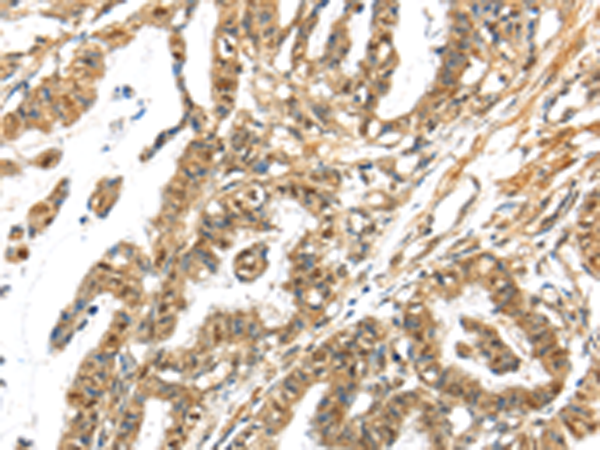

分类: 科研抗体货号: P11552别名: 5-HT3B应用: IHC反应种属: Human